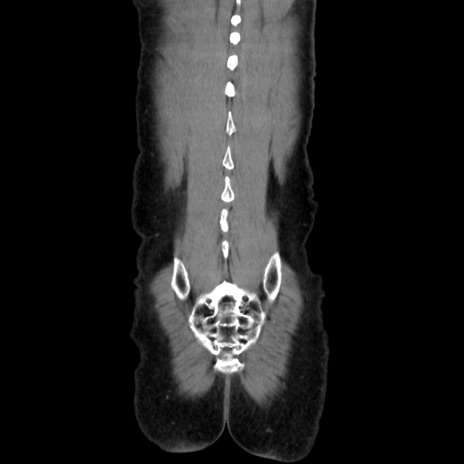

症例37(冠状断像)

【症例】40歳代 男性

【主訴】腹痛

【現病歴】4時間ほど前に電車に乗車中に臍部上より腹痛出現。徐々に増悪し起立困難となり、救急外来受診。生ものは数日食べていない。今朝お雑煮を食べた。

【身体所見】BT 36.8℃、BP 117/84mmHg、HR 91/min、SpO2 97%、苦悶様、腹部:臍上部広範囲圧痛あり、反跳痛±

【データ】WBC 8100、CRP 0.03